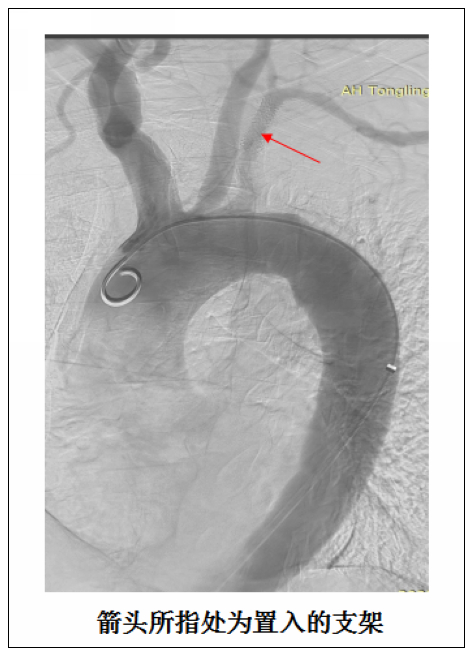

血管病区为该患者施行了左锁骨下动脉球囊扩张成型术及支架置入术。术中在左锁骨下动脉狭窄部位放置一枚直径为9mm,长度为2.5cm的支架。手术十分顺利,全程耗时不到1小时,术后患者即刻诉头晕及左上肢乏力症状明显改善,2天后顺利出院。